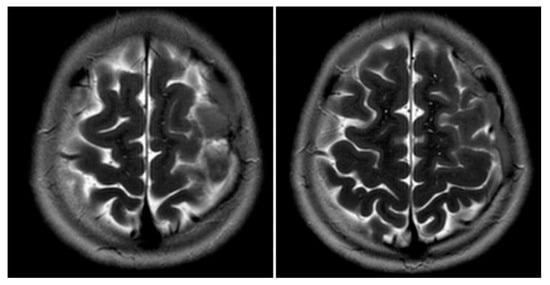

Figure 2. MRI T2WI, axial section in 2019. A very thin subdural hematoma is identified along the left convexity with mild edema noted in the subjacent perirolandic cortex. Decreased T2 signal is now identified within the cyst when compared to Figure 3 and Figure 4, which is suggestive of interval hemorrhage. These findings are consistent with a ruptured arachnoid cyst.

Figure 1 and Figure 2 reveal a change in signal of arachnoid cyst suggestive of interval hemorrhage with a thin subdural hematoma along its inferior aspect. Minimal edema in the subjacent Rolandic cortex was present. Given the patient’s stroke-like presentation, an MRA of head and neck was administered, which was found to be normal. The findings, with a comparison of the previous MRI of the patient at age 4 (Figure 3 and Figure 4), are consistent with a ruptured arachnoid cyst. No acute neurosurgical intervention was performed due to the absence of raised intracranial pressure and reduction of neurological symptoms. A routine EEG performed in the emergency department exhibited interictal epileptiform discharges over the left and right central–temporal region during drowsy and sleep states, suggestive of increased risk for partial seizures from these regions.

The patient received 500 mg levetiracetam twice daily for seizure prophylaxis. On day 2 of admission, a rapid-sequence MRI brain scan showed a stable thin subdural hematoma and a ruptured arachnoid cyst at the left frontoparietal vertex with the interval resolution of edema in the subjacent cortex. At discharge on day 3, the patient’s neurological exam remained normal without development of symptoms or signs related to acute intracranial hypertension. The patient maintained on 500 mg levetiracetam BID for seizure prophylaxis for three months. A rapid-sequence MRI brain scan at 2-week outpatient follow-up revealed a mild interval decrease in the size of left convexity subdural hematohygroma. He has had no return of rupture symptoms or concerns for seizures, including nocturnal seizures. He has occasional headaches, not sustained or requiring medication. The family express concerns regarding occasional anxiety and mild memory loss since hospitalization.